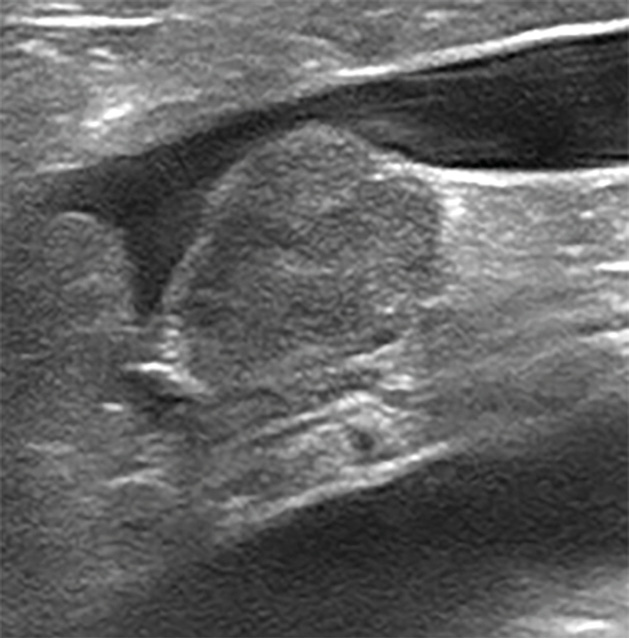

En el abdomen la glándula adrenal derecha presenta pérdida de estructura y una anchura de 17 mm; comprime la vena cava caudal, que presenta un trombo (imágenes 4 y 5). Estos hallazgos sugieren cardiomiopatía hipertrófica secundaria a hipertensión arterial sistémica y neoplasia adrenal derecha con trombosis venosa.

Imágenes ecográficas de la glándula adrenal derecha aumentada de tamaño, con pérdida de forma normal y estructura intravascular hiperecogénica adherida a vena cava caudal, compatibles con neoplasia adrenal y trombo en dicha vena.